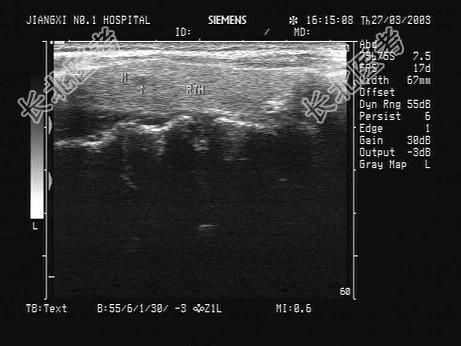

- 单项选择题患者发现颈部肿块两年余,没有明显不适。甲状腺超声显示甲状腺及血管旁异常光团, 如图。最可能的诊断为 ( )